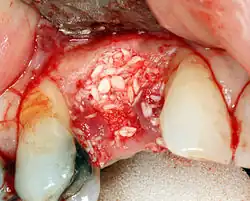

To achieve an adequate width and height of bone, various bone grafting techniques have been developed. The most frequently used is called guided bone graft augmentation where a defect is filled with either natural (harvested or autograft) bone or allograft (donor bone or synthetic bone substitute), covered with a semi-permeable membrane and allowed to heal. During the healing phase, natural bone replaces the graft, forming a new bony base for the implant.[56]: 223

Three common procedures are:[61]: 236

- Sinus lift

- Lateral alveolar augmentation (increase in the width of a site)

- Vertical alveolar augmentation (increase in the height of a site)